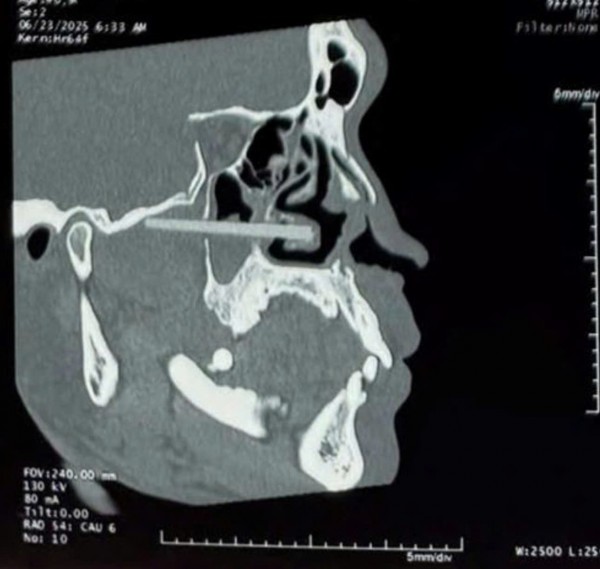

Kết quả chẩn đoán hình ảnh thấy chiếc đũa nhựa đâm vào khu vực nguy hiểm vùng mặt bệnh nhân

Kết quả cho thấy, 2 dị vật hình trụ dài khoảng 5 - 6 cm cắm sâu từ hốc mũi phải xuyên qua thành trong xoang hàm, lan tới vùng cơ chân bướm sát sàn sọ phải. Dị vật đâm vào cuốn dưới, gây viêm nhiễm mạn tính.